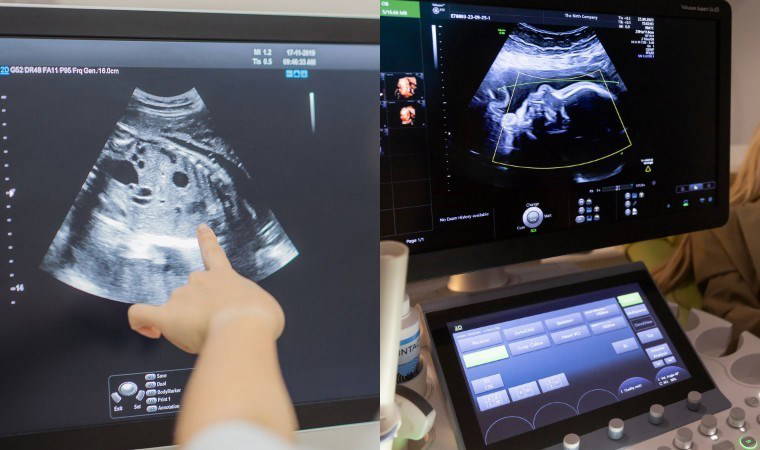

Hindistan’da 32 yaşındaki bir kadın, 35 haftalık hamileyken rutin bir tarama için hastaneye gittiğinde, doktorlar doğmamış bebeğin karnında iki fetüs tespit etti.

Hindistan’da olağanüstü nadir görülen bir tıbbi vaka tespit edildi. 32 yaşındaki bir kadın, 35 haftalık hamileyken rutin bir tarama için hastaneye gittiğinde, doktorlar doğmamış bebeğin karnında şaşırtıcı bir keşif yaptı: Bebeğin içinde iki fetüs vardı...

Başlangıçta normal seyreden hamilelik sürecinde yapılan taramalar herhangi bir sorun göstermemişti. Ancak son muayenede doktorlar, fetüsün karnında kemik içeren anormal bir yapı fark etti. Yapılan testler sonucunda, bebeğin karnında gelişimini tamamlayamayan iki hatalı biçimlendirilmiş fetüs olduğu ortaya çıktı.

Taramayı gerçekleştiren doktor Prasad Agarwal, "Bu bebekte inanılmaz derecede sıra dışı bir şey fark ettik. Karnında birkaç kemik ve fetüs benzeri bir yapı vardı. Bunun normal olmadığını hemen anladım. Dünyada çok nadir görülen fetus in fetu vakalarından biriydi" açıklamasında bulundu.